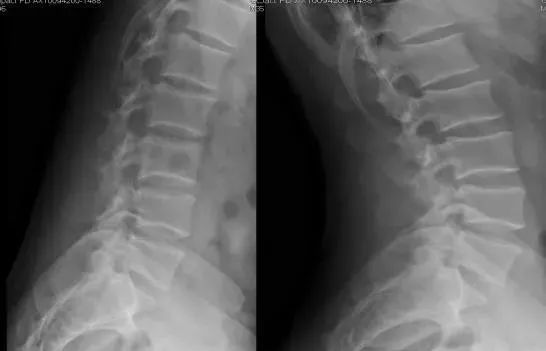

1、正位片

腰椎正位片,可显示腰椎有无侧凸,两侧横突大小有无异常(如第五腰椎横突肥大),有无移行椎(见后)、隐裂、棘突偏歪,椎间隙两侧是否等宽,椎弓根、关节突关节形状,椎弓根间距(椎管横径)大小等。

(1)腰椎棘突间联线一般均为一垂直线,如垂直线发生折曲或成角,提示椎体有移位现象。棘突偏歪曾被认为是椎间盘突出的体征。有人对此进行调查,发现一般腰椎X片和椎间盘突出腰椎X片相比,抛去侧突不计,两者无明显差异(分别为30.0%和31.3%),特别是常见的第五腰椎棘突扭曲,是发育的结果。

(2) 椎弓根形态和距离应留意,当一个椎体的椎弓根被压扁及椎弓根间距增宽时,常是椎管内神经纤维瘤的表现。关节突增大椎弓根间距小,应注意是否有退变性椎管狭窄。

(3)腰椎管横径的测量:通常测量两侧椎弓根断面内缘间最短距离作为椎管横径,此径平均值在正常人X线片自腰l至L5分别为24. 6mm,25.3mm,26.3mm,27.5mm,30.9mm,小于20mm者被认为是狭窄椎管,但其价值不如矢状径可靠。

(4)髂骨嵴间连线:在X线正位像上观察连接两侧髂骨嵴的横线与第4、5腰椎的关系。据认为髂嵴连线经L4椎体下部或其椎间盘为最稳固位置。横线与腰椎的关系结合其他参数可用以予测腰椎承受最大生物力学应力部位和退行性病变最可能发生的部位。

L4 L5之间容易发生退行性变的因素包括髂嵴间线位置过高,经过L4椎体上部;L5横突过大有移行脊椎现象。

L5骶l可能发生退行性变的因素有髂嵴横线经L5椎体和L5横突过短现象。

(5)还可观察两侧腰大肌阴影是否清晰。腰大肌阴影模糊、膨胀,常是腰大肌脓肿(结核)的表现。